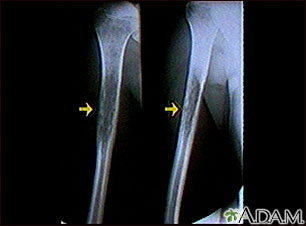

This x-ray shows a malignant bone tumor (Ewing sarcoma) of the upper arm bone (humerus). This type of tumor usually occurs during childhood and adolescence.